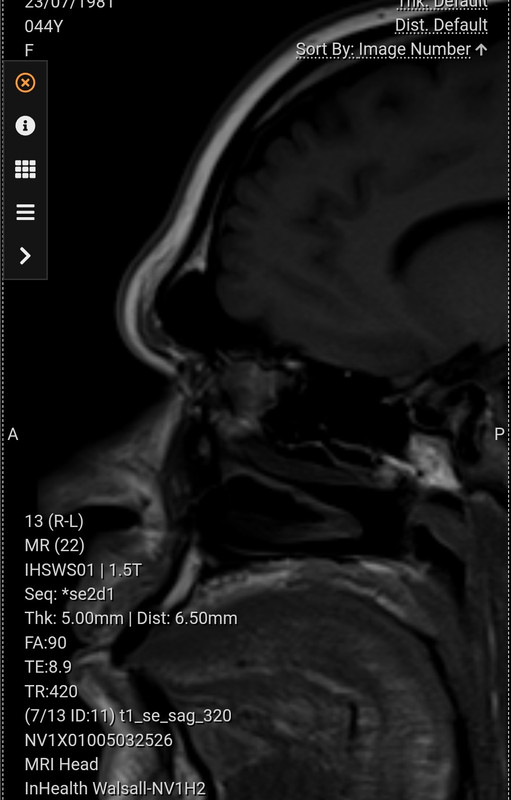

I got my MRI scans back today. I was surprised to see a brain inside and that actually fills most of the space! Not sure how that's true but it is 😀

It will help my surgeon for sure as my brow bone is huge. That's a big chunk to come out, flatten and go back. This type 3 reduction is scary in thought!

Congratulations on Proof of Brain, Charlotte! I printed mine and laminated it so I could show it to people who doubt me.

So, do they un-cap it, shave the top and bottom down, then re-cap it?

I had a craniectomy (in back), so they took out a chunk of skull for access and then basically closed it up with cellophane. I wish I'd asked to have that piece of skull.

Quote from: Pema on January 20, 2026, 04:31:03 PMSo, do they un-cap it, shave the top and bottom down, then re-cap it?

That's pretty much it. Flatten as much as possible and set it back. Screws and titanium plates are involved! I've heard some surgeons wire it back in, but this is thought to be inferior these days.